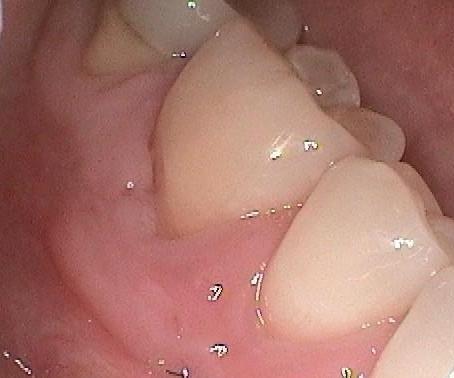

Here is a patient who has advanced recession with the roots of the teeth becoming exposed.

In the picture below, the:

GREEN LINE is where the gum tissue should be

RED LINE is where gum tissue has receded

BLUE LINE shows the transition between the two tissue types.